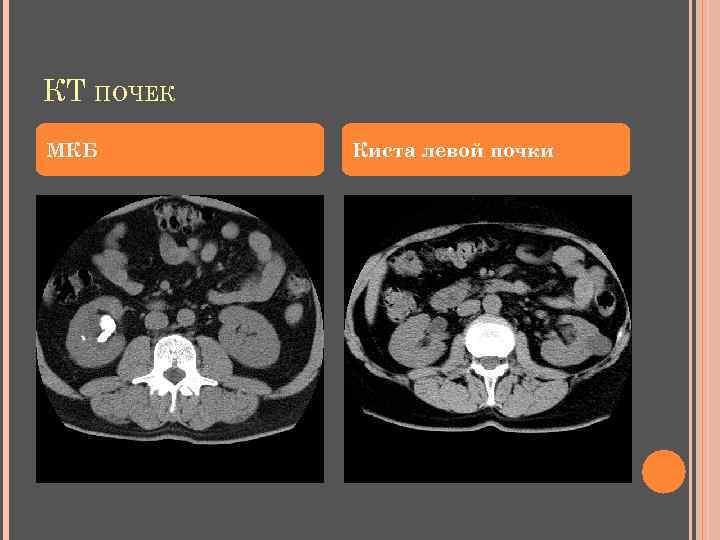

КТ ПОЧЕК МКБ Киста левой почки